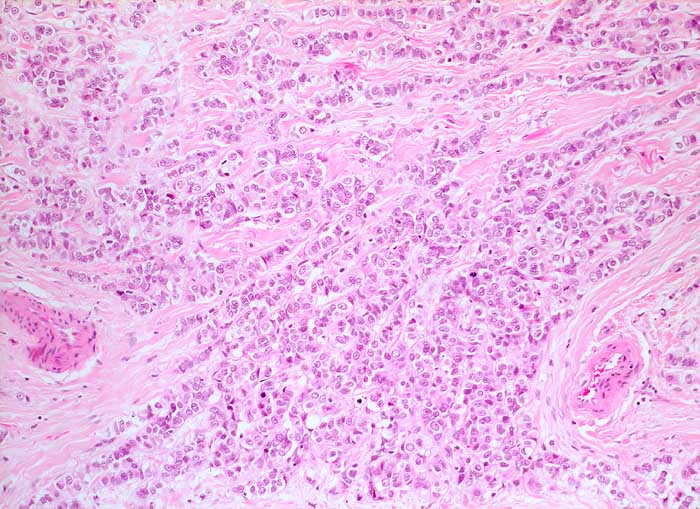

Maligner Aszites: lobuläres Mammakarzinom

Lobuläre Mammakarzinome sind im Gegensatz zu den invasiv duktalen Karzinomen im Erguss viel weniger leicht erkennbar. Die Tumorzellen sind etwa so gross wie Mesothelien oder Makrophagen. Sie liegen einzeln oder in kleinen Gruppen und bilden zeilenförmige Verbände. Ihre Kerne sind hyperchromatisch, diskret entrundet oder gekerbt und auch von der Kernstruktur her kaum von Mesothelien oder Makrophagen unterscheidbar. Unten werden zwei verschiedene Fälle gezeigt. Der erste Fall zusätzlich mit histologischer Korrelation.